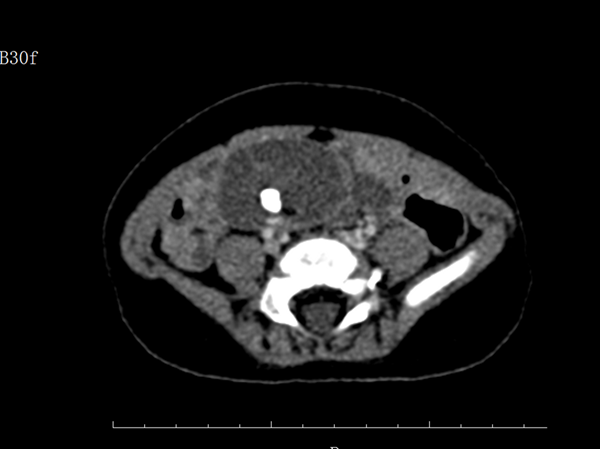

入院后通過完善腹部CT檢查,進(jìn)一步顯示腹腔內(nèi)的包塊是一畸胎瘤,直徑達(dá)4.3cm。左側(cè)隱睪,腹腔畸胎瘤,一個小孩同時(shí)兩種病癥?我院小兒外科醫(yī)師在了解病情后,高度懷疑此畸胎瘤是左側(cè)腹腔型的隱睪來源,這種案例極為少見。

患兒術(shù)前腹部CT